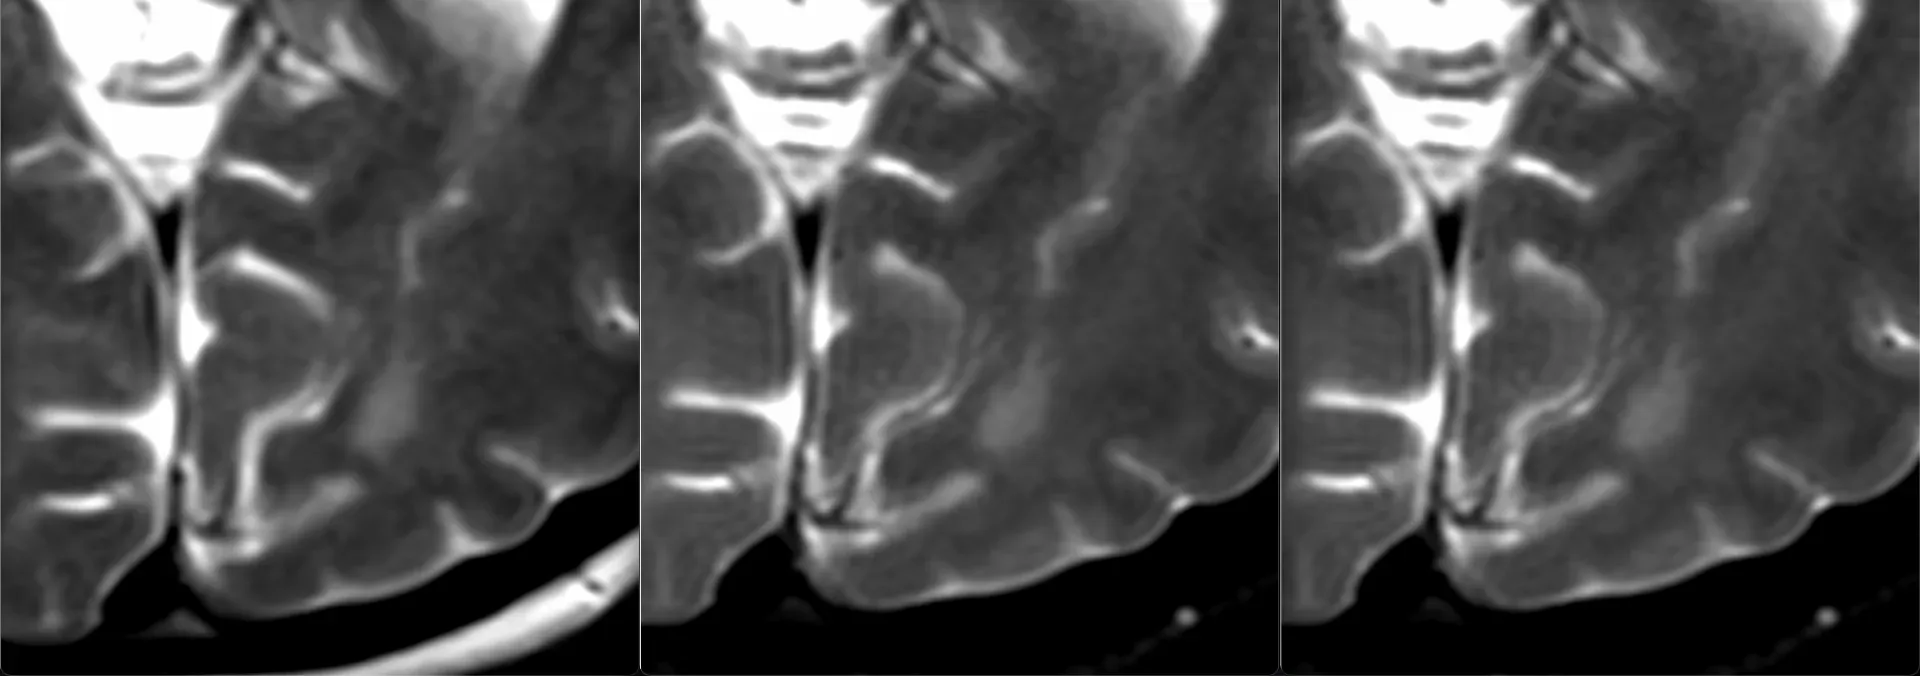

Плексиформная кожная нейрофиброма у мужчины 34 лет с известным диагнозом Нейрофиброматоз первого типа. В отличие от типичных мишеневидных поражений, идущих вдоль крупных нервов при глубоких плексиформных нейрофибромах, поверхностные плексиформные нейрофибромы при НФ1, как правило, асимметричны, имеют немишеневидную структуру, не обладают узловатой или фасцикулярной морфологией и поражают кожу, а не только клетчатку. У этого пациента, как он говорит, шишка на внутренней поверхности левого бедра в течение многих лет, не меняется.